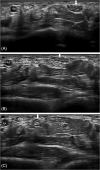

Median nerve instability in the wrist: Ultrasound diagnosis

Instability of the nerves, which does not follow traumatic injury, is relatively rare. The ulnare nerve is most typically involved. Median nerve instability is far less common. The identification of instability of the median nerve in the wrist is definitely an indication for ultrasound examination before carpal tunnel release.